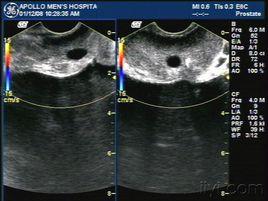

射精管囊腫是由於精路梗阻,射精管擴張、膨大引起的,並且囊腫與精囊、輸精管和後尿道相通。多為繼發性,囊液內含有果糖和(或)正常精子,且囊內常有結石。射精管囊腫的症狀包括出血、感染、惡變、鈣化以及結石等,可繼發不育、血精症、射精量減少、射精痛、直腸區不適、尿瀦留以及在精阜水平對射精管和尿道造成壓迫而引起精囊充血等較嚴重的併發症,治療不及時有可能引發不育。